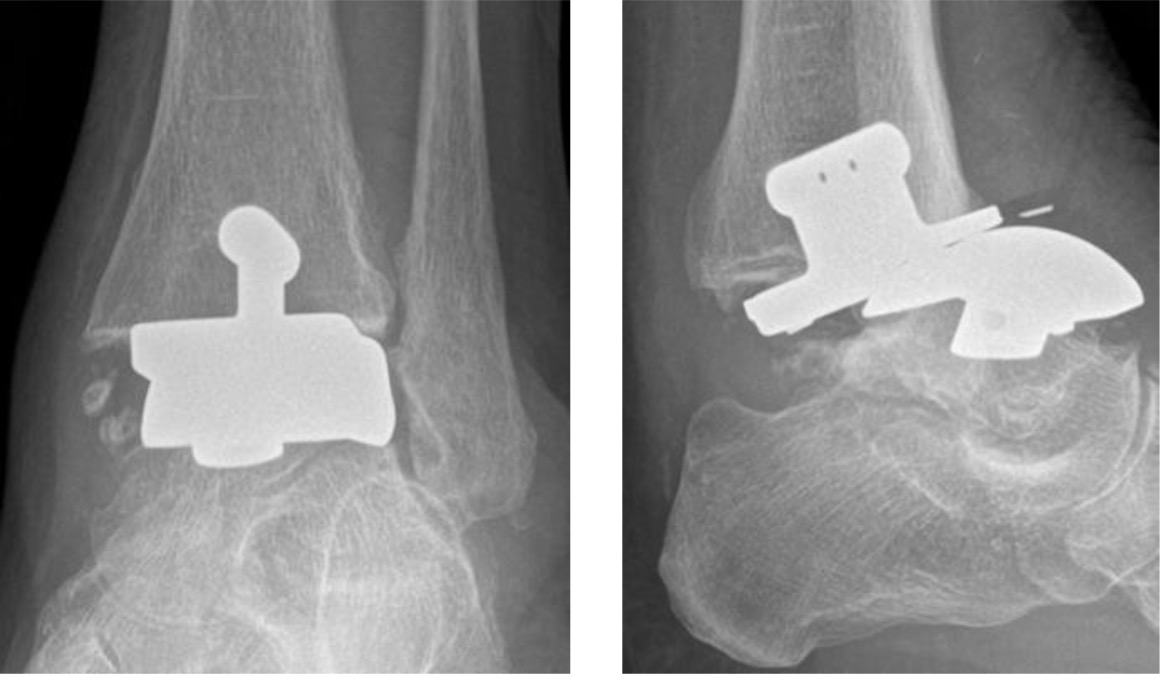

Subluxation of failed total ankle replacement

Metalware loosening

Radiographic signs of chronic low-grade infection may be identical to mechanical aseptic loosening including periprosthetic lucency, subsidence and periosteal reaction.

Comparison with prior radiographs is important to assess for progression of changes that may indicate hardware failure.